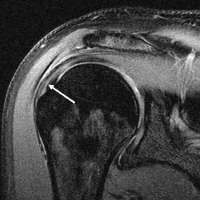

MRI of normal shoulder intratendinous signal

MRI of rotator cuff full-thickness tear

Tears of the rotator cuff tendon are described as partial or full thickness, and full thickness with complete detachment of the tendons from bone.

Shoulder pain is variable and may not be proportional to the size of the tear.